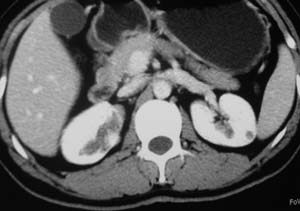

以下是引用子期在2010-3-19 20:47:00的发言:[br]血管畸形的ct增强应该有明显强化,本例并不相符合。本例双肾局部的略低密度影,累及肾盂,局部皮质明显变薄、内陷,增强扫描有轻度的强化,应考虑为炎性病变,患者为年轻男性,累及双肾的感染以结核较常见,可以没有明显的临床症状,尿中有时候也并不能查出什么;肾脓肿常有明显感染中毒症状,本例不符,另外一般的肾盂肾炎或肾小球肾炎通过小便就可确诊,其它还不能排除的是黄色肉芽肿性肾盂肾炎,然而单凭ct一般也很难鉴别。